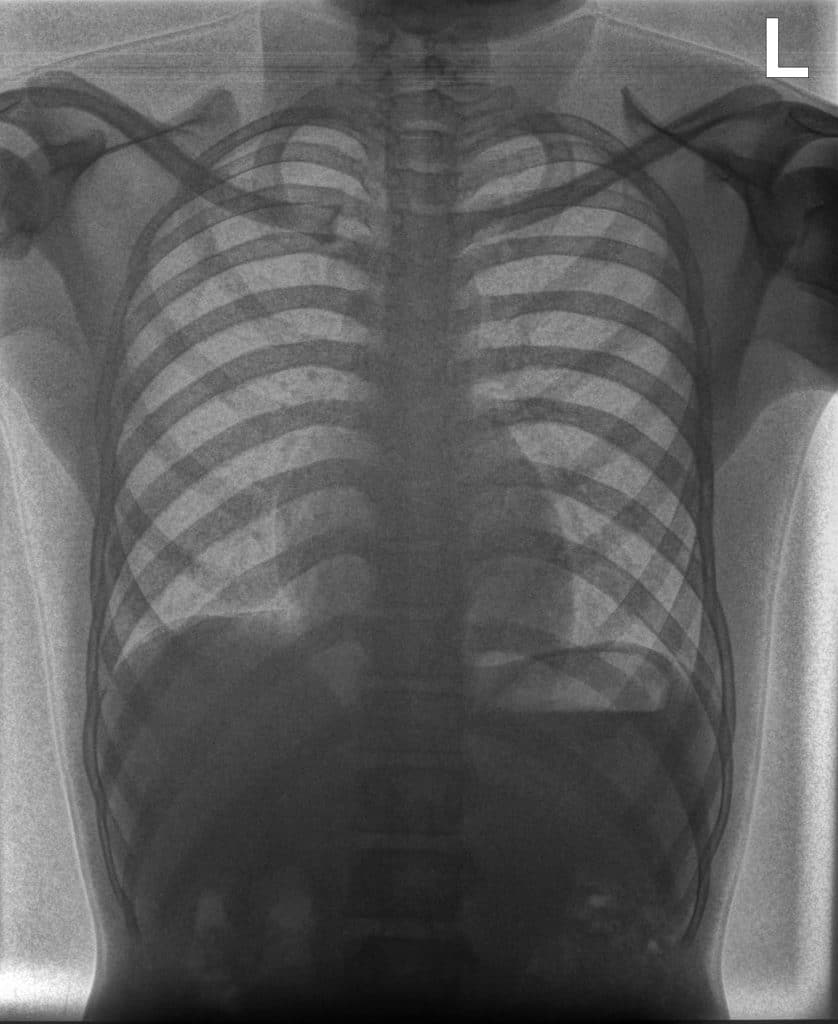

Reveal™ detectors generate three images from a single X-ray exposure:

- conventional radiograph

- bone image

- soft-tissue image

These images allow clinicians to examine anatomical structures from different perspectives and may provide additional insight when evaluating radiographs in environments where other imaging modalities are not available.